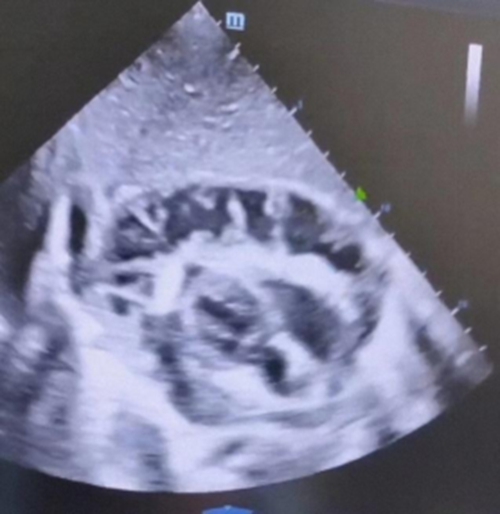

然而,通過(guò)完善

抽血、床旁心臟彩超等檢查

醫(yī)生又發(fā)現(xiàn)了更加嚴(yán)重的問(wèn)題

除了大量心包積液外,還伴有廣泛的纖維沉積、分隔,血液檢測(cè)白細(xì)胞危急值,高于正常上限數(shù)倍!小月極有可能患上了少見且兇險(xiǎn)的——化膿性心包炎!